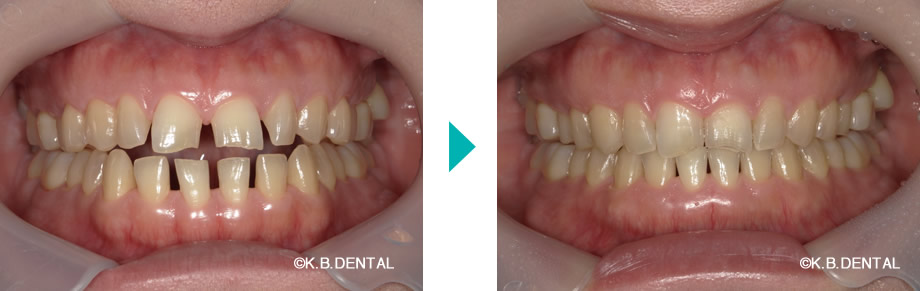

空隙が目立つ症例(前歯のすきっ歯)

| 主訴 | 歯並びがガタガタ、歯が隙間だらけで何とかしたい |

|---|---|

| 診断名 | 舌癖に起因した歯列不正 |

| 初診時年齢/性別 | 32歳女性 |

| 装置 | マウスピース矯正(インビザラインGo)+舌癖コントロール |

| 抜歯/非抜歯 | 非抜歯 |

| 治療期間 | 約1年 |

| 費用 | 約70万円(税別) |

| リスク副作用等 | 矯正歯科治療のリスク副作用について |